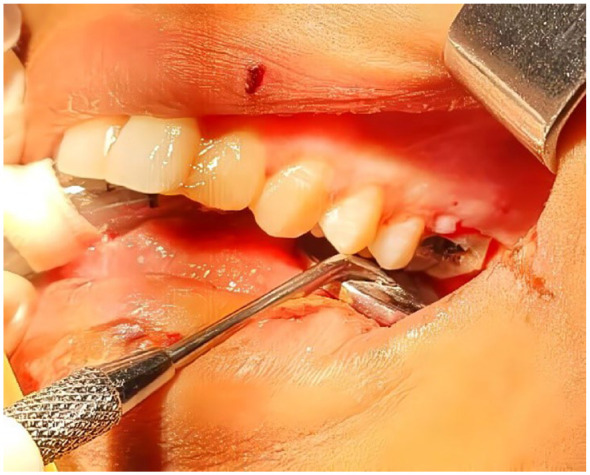

Case reports: A 22-year-old female and 30-year-old male patients, both with no significant medical history, presented with subdural empyema and intracranial epidural abscess, respectively, both complicating pan-sinusitis of dental origin. Successful outcomes were achieved with surgical drainage of the lesions, antibiotic therapy, and extraction of affected teeth. Female patient underwent further management for neurological sequelae, while male patient was discharged without neurological complications.

Abstract Image